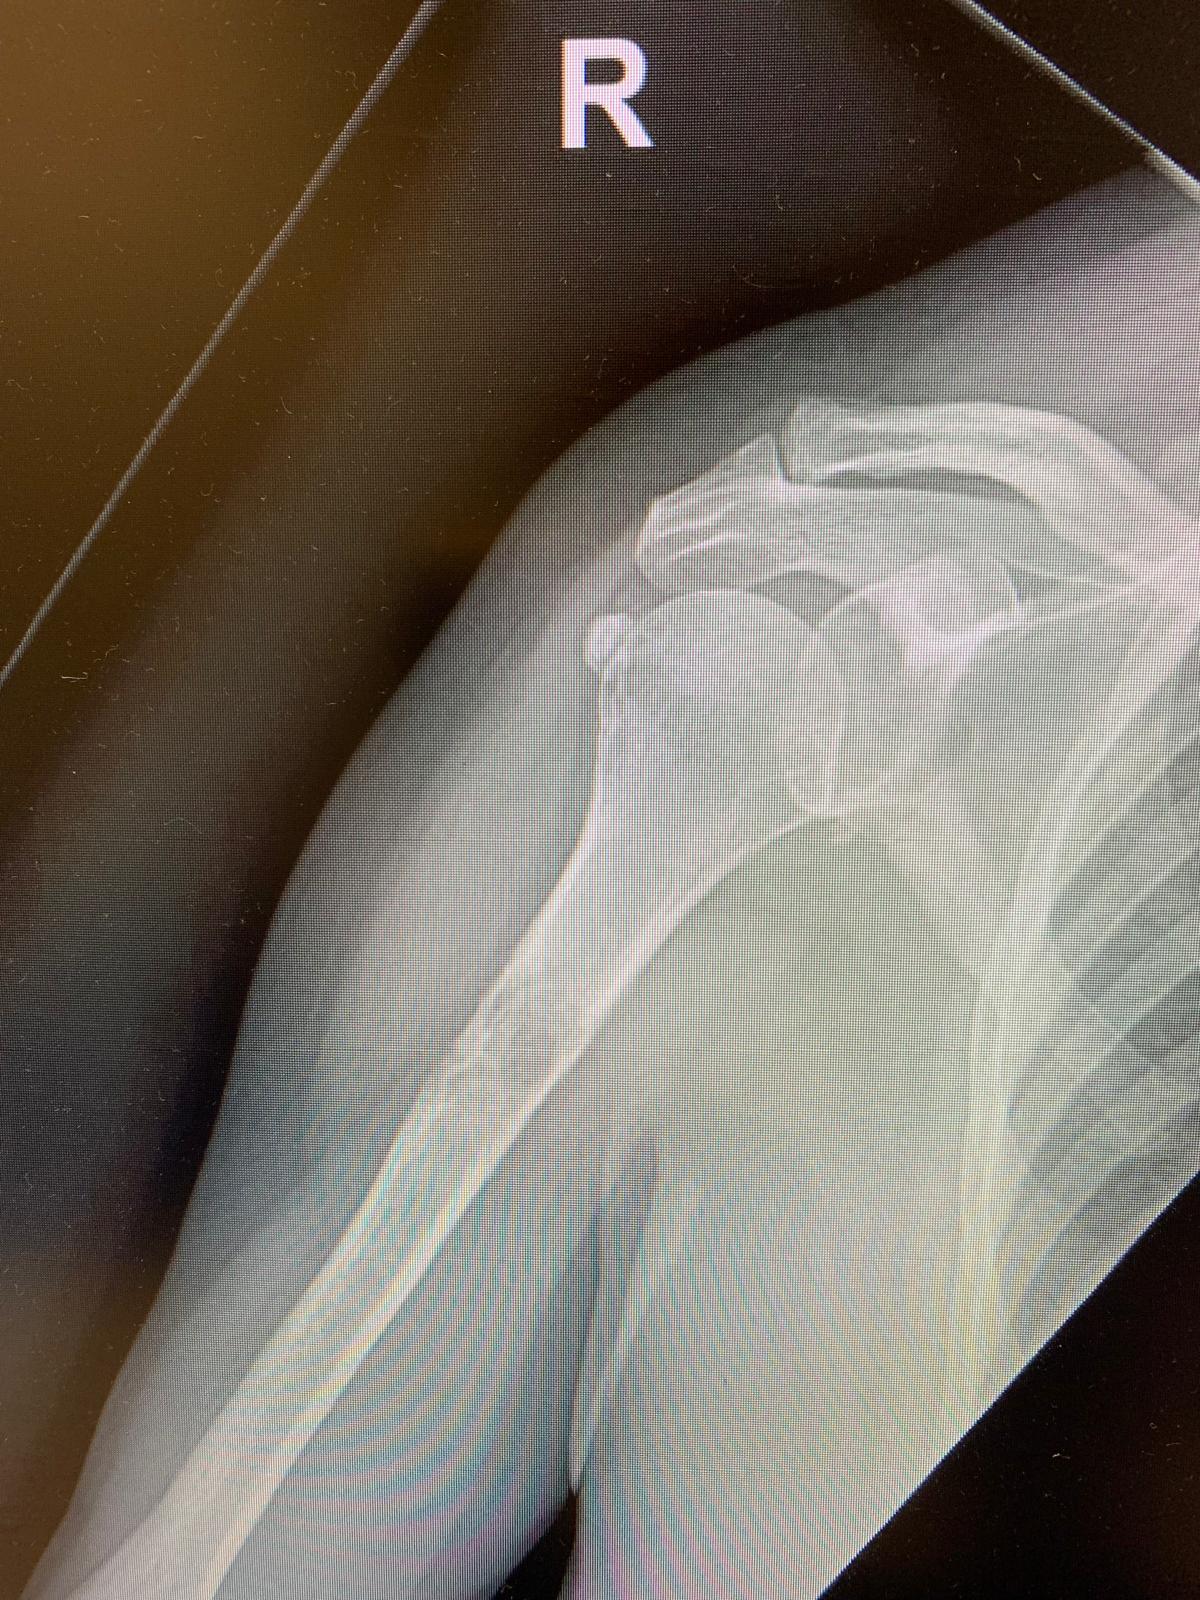

En su primera consulta de Atención Primaria se pauta analgesia sin otra prueba complementaria. En la consulta de seguimiento, dada la ausencia de mejora del dolor, se solicita radiografía de hombro de carácter normal. Se realiza la radiografía el 14/08/2024. La paciente decide acudir a Urgencias el 13/09/2024 ante la persistencia de la clínica. No refiere nueva clínica sistémica.

En la consulta de urgencias se revisa radiografía realizada y se objetiva lesión lítica a nivel de húmero. Dadas las características radiológicas y el antecedente oncológico se debe sospechar de malignidad como primera posibilidad diagnóstica.

La paciente ingresa en Hospitalización Parcial y se confirma la presencia de múltiples metástasis óseas (húmero derecho, rama isquiopubiana izquierda, acetábulo y cabeza femoral izquierda). Se inicia tratamiento con bifosfonatos a la espera del resultado de Anatomía Patológica de la biopsia humeral realizada el 02/10/2024.